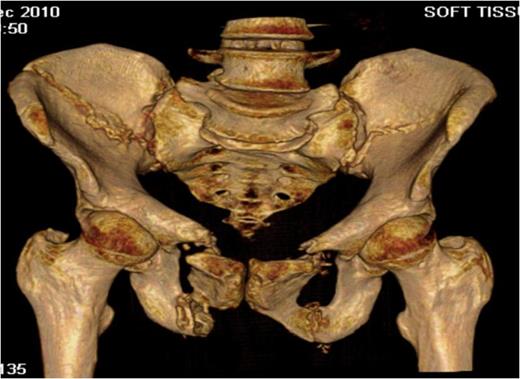

A 57 year old woman slipped while shopping resulting in a fall, where-upon her right hip flexed to 90 degrees and her left hip extended to 90 degrees, to a point where her perineum came to rest on the floor. This particular fall resulted in a twisting or torque like force being transmitted through her pelvis as she fell. She was helped up after the fall and was able to mobilise with assistance. She attributed the increased pain that she was experiencing to aggravation of her long standing back complaint. Prior to her fall she had attended the spinal clinic for her back pain and was scheduled for a bone scan with a view to progressing to facet joint blocks. On attendance at the spinal clinic following her scan it was noted that her low back pain had become more pronounced and she required walking aides in the form of crutches to mobilise. On reviewing the bone scan, multiple areas of increased uptake were noted in the bony pelvis. Further imaging, both plain film and computed tomography (CT) (Fig.1 & Fig. 2) revealed extensive pelvic fractures with displaced bilateral superior and inferior pubic rami fractures and bilateral posterior ring crescent fractures. Her past medical history was significant only for her aforementioned back pain. She had no previous fractures and prior to her fall worked as a care assistant.

Three-dimensional CT reconstruction showing both the bilateral crescent and superior and inferior pubic rami fractures